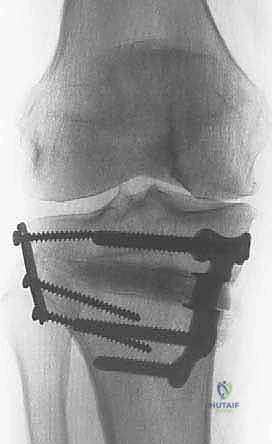

باستخدام أدوات دقيقة ومناشير جراحية متطورة، يتم عمل قطع غير مكتمل في عظمة الساق. هناك طريقتان رئيسيتان:

* الشق المفتوح (Opening Wedge): يتم فتح العظم من الداخل وإضافة طعم عظمي (صناعي أو طبيعي) لملء الفراغ وتعديل الزاوية. وهي الطريقة الأكثر شيوعاً حالياً.

* الشق المغلق (Closing Wedge): يتم إزالة إسفين (مثلث) صغير من العظم من الجهة الخارجية وإغلاق الفراغ.

4. تعديل المحور:

يتم فتح العظم تدريجياً وببطء شديد حتى الوصول إلى الزاوية التي تم حسابها في التخطيط الرقمي قبل الجراحة.